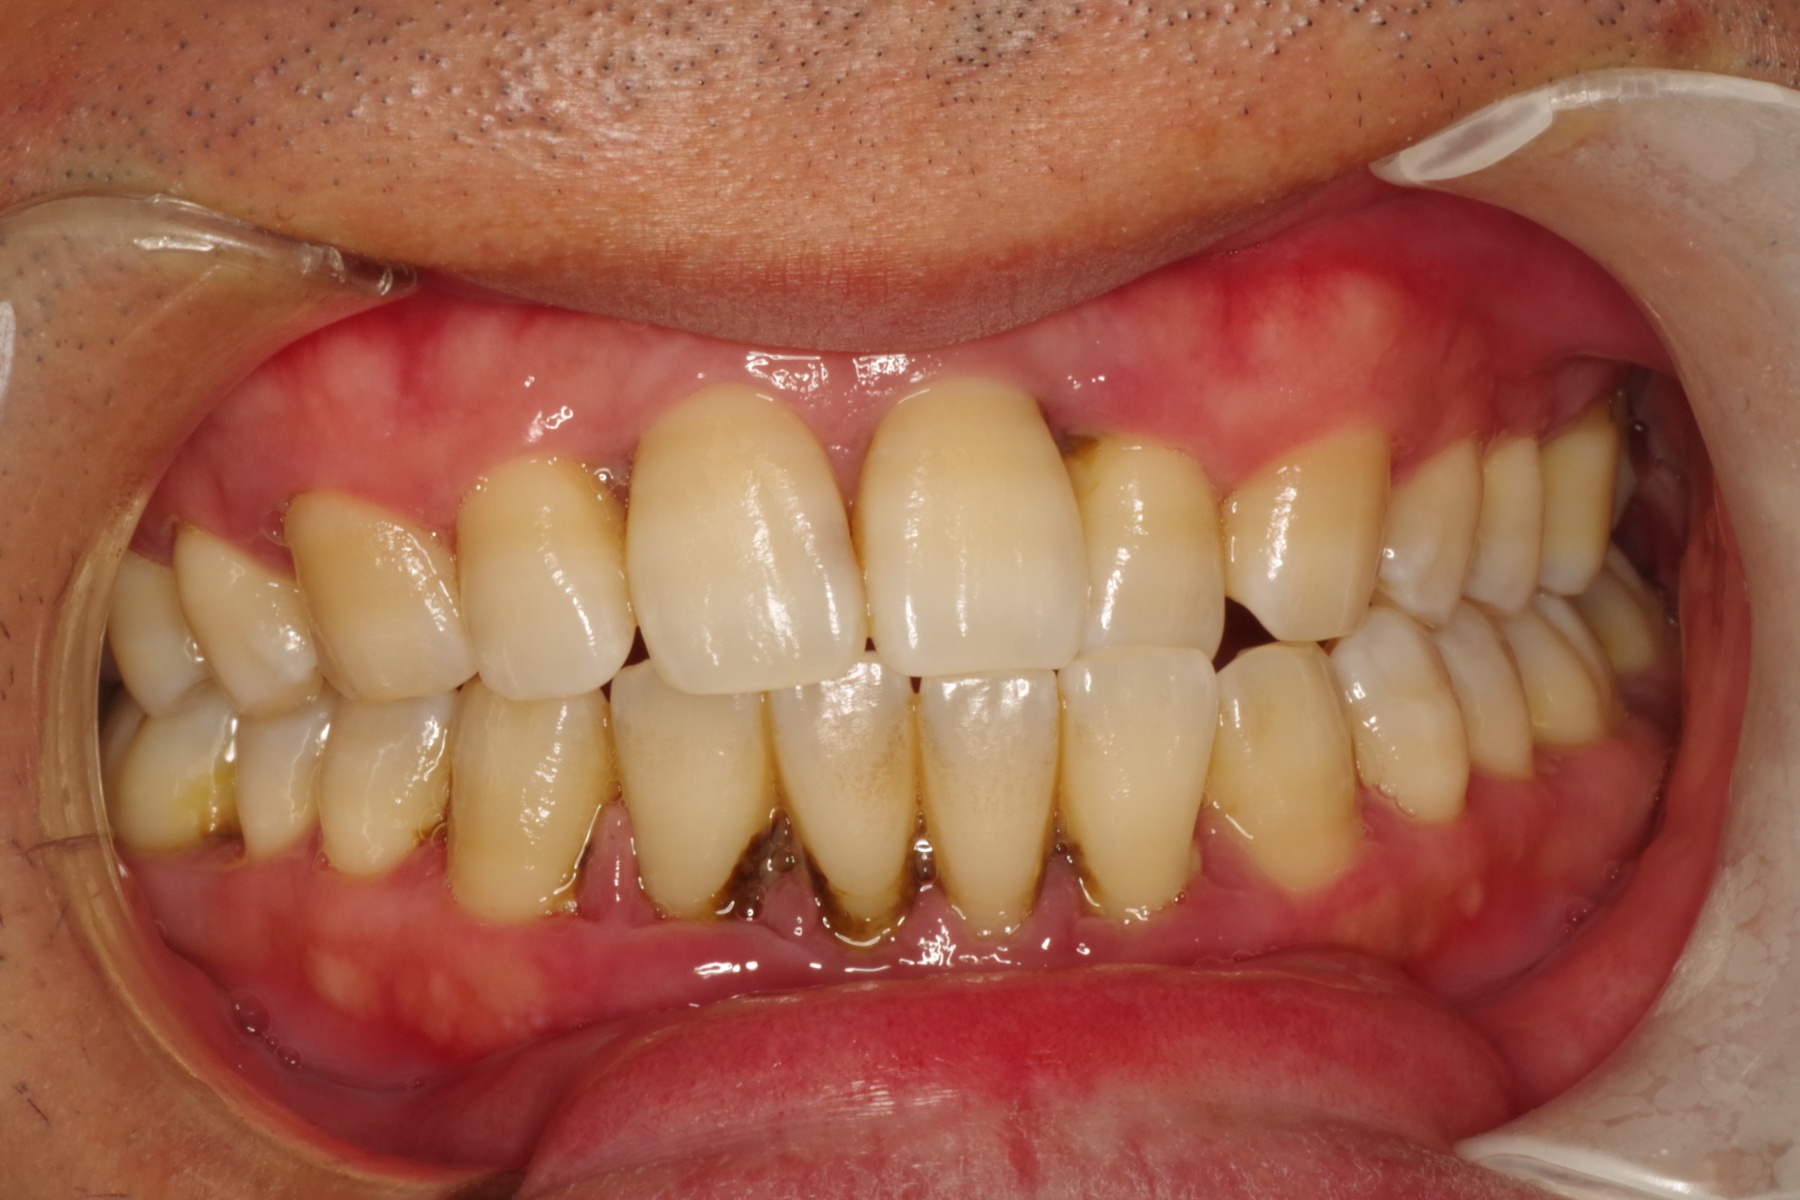

歯肉が赤く腫れる感じは・・。

歯周病が進むと顎の骨を溶かし、最悪の場合、歯が抜けてしまいます。

歯周病は虫歯より痛みが出るのが遅いため、早期発見が大切です。

当医院では歯茎の検査やお口全体のレントゲン写真を用い、歯周病の有無を確認いたします。

歯周病の程度により治療内容や診察回数が異なりますのでまずはご相談下さい。